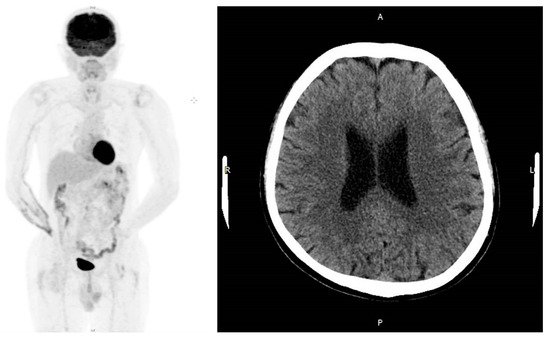

2. Case Presentation